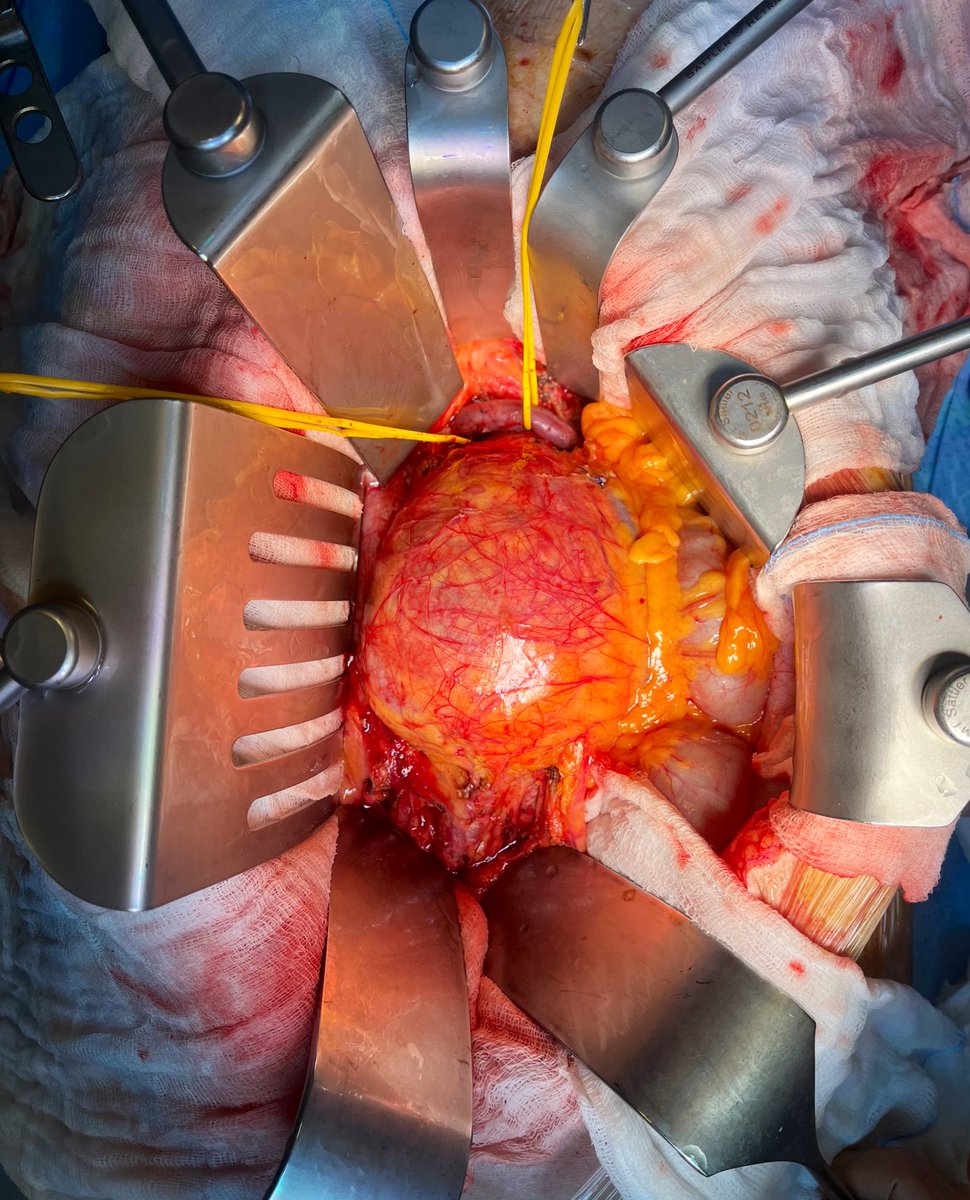

Type II endoleak with progressive sac enlargement. The first #inthebucket of 2024! 🗑️ #veterosurgery

Type IA 120x130mm symptomatic. #veterosurgery #inthebucket